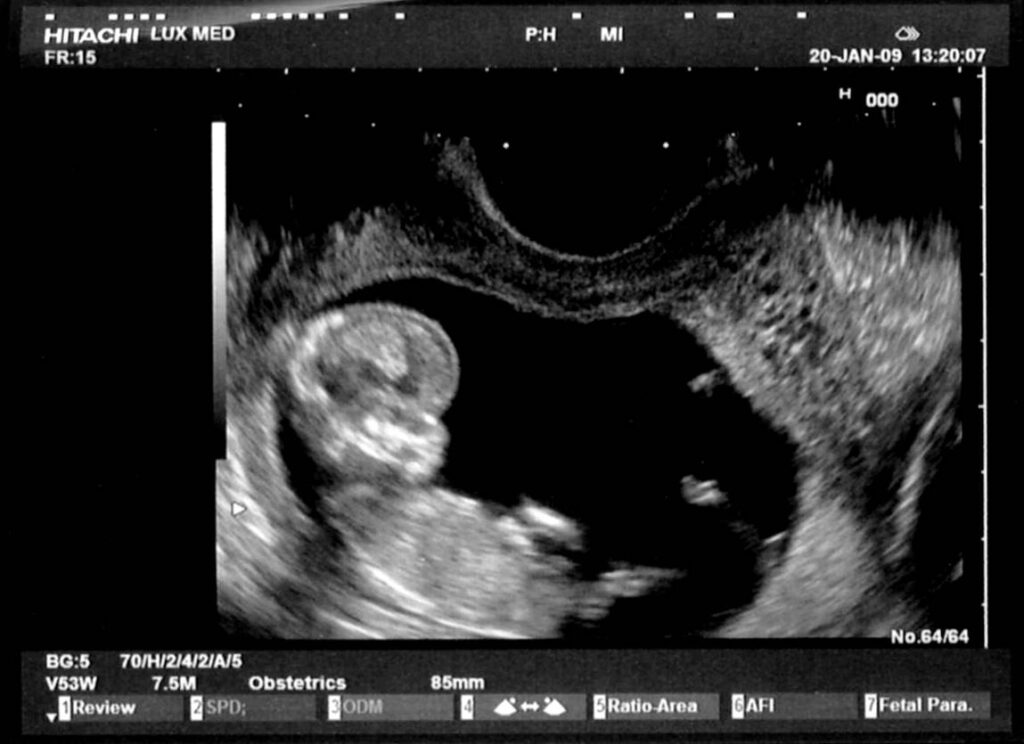

Perhitungan Dengan Metode USG

Dalam perkembangan teknologi kedokteran, USG atau dalam bahasa kedokteran disebut dengan ultrasonologi merupakan kemajuan teknologi kedokteran yang amat sangat membantu. USG memiliki tingkat akurasi yang lebih tinggi dengan mengukur ukuran tengkorak, ukuran jantung, panjang janin, ginjal dsb. Melalui USG ini bunda akan dapat melihat secara langsung bagaimana perkembangan janin dalam kandungan, bahkan seiring perkembangan teknologi USG tidak hanya dalam 2 dimensi akan tetapi juga secara 3 dimensi.

Dengan demikian maka metode USG ini dapat digunakan sebagai cara menghitung usia kehamilan yang paling akurat. Dalam menghitung usia kehamilan dengan metode USG, metode ini menggunakan 3 cara dalam 3 tahap perkiraannya, yaitu :

- Gestational Sac (GS)

Cara Gestational Sac ini dilakukan dengan cara mengukur diameter kantong kehamilan. Metode ini dilakukan pada awal kehamilan setelah dipastikan kehamilan dari ciri-ciri hamil yang dialami sang ibu. Biasanya metode ini dilakukan pada usia kehamilan 6-12 minggu. - Grown Rump Length (GRL)

Cara Grown Rump Length ini dilakukan dengan cara mengukur jarak antara kepala dan bokong pada janin. Biasanya metode ini dilakukan perkiraan usia 7-14 minggu. - Biparietal Diameter (BPD)

Cara Biparietal Diameter ini dilakukan dengan cara menghitung diameter kepala janin pada usia kehamilan dengan perkiraan 12 minggu. Metode ini yang kemudian akan sering digunakan untuk mengontrol kondisi janin dalam kandungan, apakah perkembangan sudah sesuai dengan perhitungan metode kalender ataukah belum.